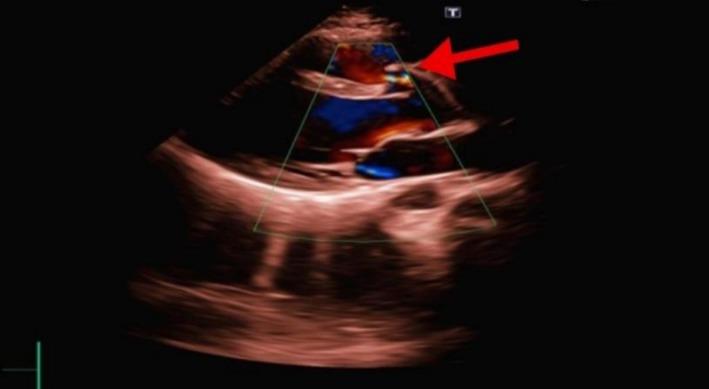

An aorto-cameral fistula (ACF) is a rare abnormal communication between the aorta and a cardiac chamber, often resulting from trauma, ruptured sinus of Valsalva aneurysms, infective endocarditis, aortic dissection, or iatrogenic causes. Clinical presentations vary from asymptomatic cases to severe hemodynamic compromise, including heart failure, arrhythmias, and sudden cardiac death. We present a 17-year-old female with exertional dyspnea and fatigue, 9 years after a penetrating chest trauma. Transthoracic echocardiography and cardiac CT revealed an 8 mm fistulous connection between the right sinus of Valsalva and the right ventricular outflow tract. Surgical repair under cardiopulmonary bypass successfully closed the defect with 5-0 Prolene sutures, confirmed intraoperatively without residual shunting or aortic valve dysfunction. The patient recovered uneventfully and was discharged on postoperative day four. This case highlights the diagnostic challenges of chronic traumatic ACF and emphasizes the importance of multimodal imaging for early detection and timely surgical intervention to prevent long-term hemodynamic deterioration. Given the potential for delayed complications, clinicians should maintain a high index of suspicion for post-traumatic cardiac fistulas, even years after the initial injury.

主动脉-心腔瘘(ACF)是一种罕见的主动脉与心腔之间的异常连通,通常由外伤、瓦氏窦瘤破裂、感染性心内膜炎、主动脉夹层或医源性原因引起。临床表现从无症状到严重的血流动力学障碍不等,包括心力衰竭、心律失常和心源性猝死。我们报告一例17岁女性,在胸部穿透伤9年后出现劳力性呼吸困难和疲劳。经胸超声心动图和心脏CT显示,瓦氏窦右窦与右心室流出道之间存在一个8毫米的瘘管连接。在体外循环下进行手术修复,成功地用5-0普罗林缝线闭合了缺损,术中证实无残余分流或主动脉瓣功能障碍。患者恢复顺利,术后第四天出院。该病例突出了慢性创伤性ACF的诊断挑战,并强调了多模态成像对于早期检测和及时手术干预以防止长期血流动力学恶化的重要性。鉴于可能出现延迟并发症,临床医生即使在初始损伤多年后,也应高度怀疑创伤后心脏瘘。